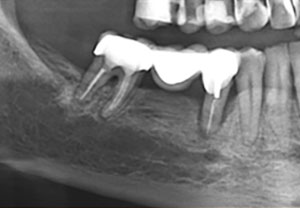

Δυστυχώς υπάρχουν περιπτώσεις όπου η νεκρωτική βλάβη του πολφού ενός δοντιού, συνοδεύεται από έξοδο των μικροβίων από το σηπτικό ριζικό σωλήνα στους περιακρορριζικούς ιστούς. Η χρόνια ακρροριζική περιοδοντίτιδα όταν χαρακτηρίζεται από μεγάλες δομικές αλλοιώσεις των περιακρορριζικών ιστών, μεγάλη απορρόφηση του φατνιακού οστού που στηρίζει το δόντι, δεν μπορεί να αντιμετωπιστεί πάντα με τη συντηρητική ενδοδοντική θεραπεία του υπαίτιου δοντιού.

Προκειμένου να παραμείνει το δόντι λειτουργικό στο φραγμό και να μη προβούμε στην αφαίρεσή του, προσπαθούμε να συνδυάσουμε την ενδοδοντική θεραπεία με τη χειρουργική αφαίρεση όλων των παθολογικών στοιχείων που εντοπίζονται στους περιακρορριζικούς ιστούς. Η μικροχειρουργική επέμβαση πραγματοποιείται από τον γναθοπροσωπικό χειρουργό κ. Βήλο Γιώργο.

Ατελής ενδοδοντική θεραπεία που οδήγησε σε περιακρορριζική καταστροφή.

Η επανάληψη της ενδοδοντικής θεραπείας δεν οδήγησε σε πλήρη επούλωση της βλάβης,

καθώς είναι αναγκαία και η περιοδοντική θεραπεία του δοντιού.

Χρόνια φλεγμονώδης περιακρορριζική βλάβη, κυρίως,

λόγω ενδοδοντικής αιτιολογίας. Μετά την ενδοδοντική θεραπεία

ακολούθησε περιοδοντική θεραπεία.

Δύο χρόνια μετά, παρατηρείται πλήρης εξαφάνιση της βλάβης.